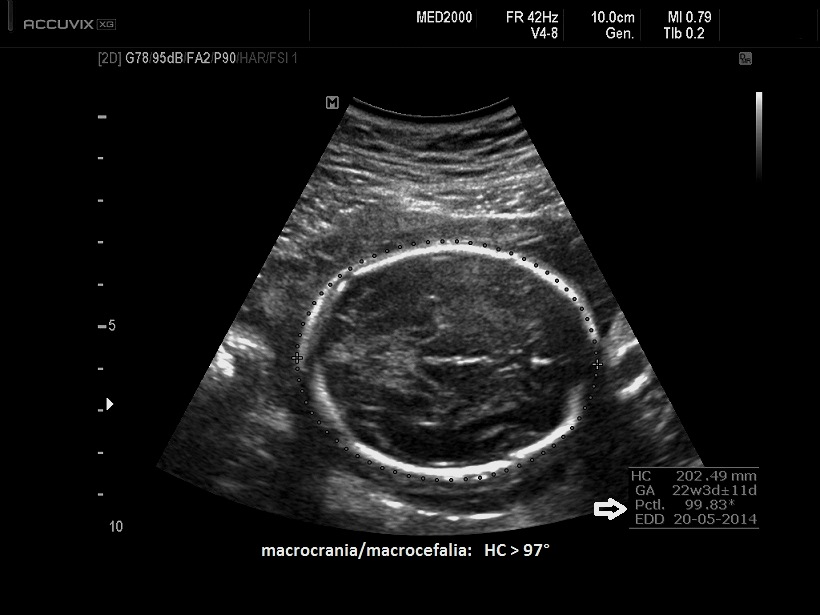

• anomalie cranio-facciali (macrocrania con bozze frontali prominenti, fronte alta e larga, naso a sella, ipertelorismo).

3. macrocefalia,